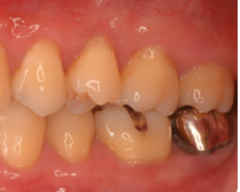

歯周病が進行し、グラグラして物が嚙めず、抜歯してインプラントにしていくことに。

インプラントはストローマンを使用、上部構造はジルコニアセラミックス

費用は2本で総額40万円(税込44万円)(他院の相場だと税込88万円位です)